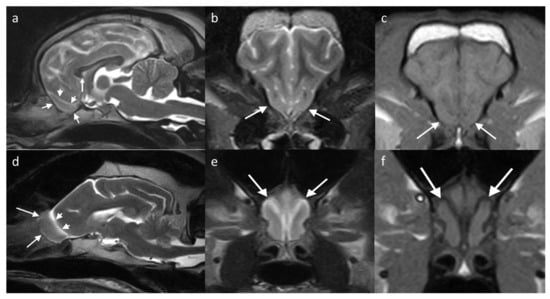

Regarding g the cat, there are fewer studies assessing the range of anatomic variation of the OB seen on imaging. Most cats have the OB located rostral to the brain, similar to dolichocephalic dogs. Some brachycephalic cats have a less protuberant OB, with breeds such as Persians described as having shortened OBs that are ventrally and laterally displaced [80], similar to brachycephalic dogs. Dilation of the olfactory recess of the lateral ventricle is identified as an incidental finding in normal cats [70]. In this study, 11% of cats with olfactory recess dilation were clinically normal and, therefore, this dilation was considered an incidental discovery in the absence of other MRI findings. There was, however, a greater likelihood of having bilateral dilation if it was secondary to ventriculomegaly or an intracranial space-occupying lesion. The normal appearance on MRI of the OB in a cat with normal OBs and of a cat with a dilated olfactory recess but presumptively clinically normal are included in Figure 6.

Figure 6. MRI brain of two cats, showing the location and appearance of the OBs (white arrows). (a,d) T2W sagittal/slightly parasagittal to line through with the OB; (b,e) T2W transverse at the level of the OB; and (c,f) T1W transverse equivalent. (ac) is of a domestic short hair cat (8-year-old) showing that the OBs are located protruding from the rostral aspect of the brain, extending slightly more rostrally than in dogs. On the transverse view, the OBs are noted between the globes. (df) is of a 16-year-old cat with a common variation of anatomy, showing a distension of the olfactory recess of the lateral ventricles, leading to a T2W hyperintense and T1W hypointense central ovoid structure within the OB, which connects to the lateral ventricle via a thin stalk (white arrowheads).